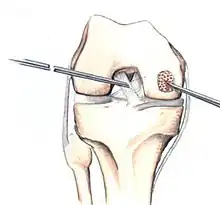

Intact lesions

If non-surgical measures are unsuccessful, drilling may be considered to stimulate healing of the subchondral bone. Arthroscopic drilling may be performed by using an antegrade (from the front) approach from the joint space through the articular cartilage, or by using a retrograde (from behind) approach through the bone outside of the joint to avoid penetration of the articular cartilage. This has proven successful with positive results at one-year follow-up with antegrade drilling in nine out of eleven teenagers with the juvenile form of OCD,[53] and in 18 of 20 skeletally immature people (follow-up of five years) who had failed prior conservative programs.[54]

The three methods most commonly used in treating full thickness lesions are arthroscopic drilling, abrasion, and microfracturing.

Similar to OATS, arthroscopic articular cartilage paste grafting is a surgical procedure offering cost-effective, long-lasting results for stage IV lesions. A bone and cartilage paste derived from crushed plugs of the non-weight-bearing intercondylar notch can achieve pain relief, repair damaged tissue, and restore function.[61]